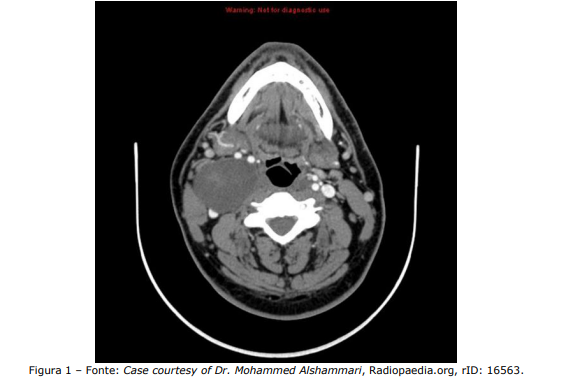

Homem, 45 anos, vem à consulta no ambulatório de cirurgia de cabeça e pescoço por queixa de abaulamento cervical em topografia jugulocarotídea alta à direita, assintomático. Refere massa há cerca de 4 anos, com crescimento progressivo, porém lento. Nega episódios inflamatórios prévios. Ao exame, a massa é fibroelástica, indolor, móvel no sentido anteroposterior, porém não no craniocaudal. Nesse sentido, analise a Figura 1 a seguir, em que a TC é mostrada:

Em relação ao caso, assinale a alternativa que indica a hipótese diagnóstica mais provável.